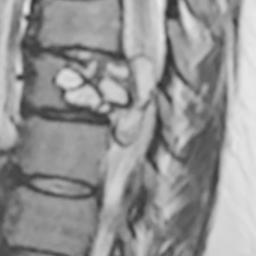

Woman's tingling legs turned out to be parasite in her back

The woman who came into the emergency room in Dijon, France, said she had been having difficulty riding her horse for three months. Her symptoms had only gotten worse, from weakness to falls to feeling electric shocks in both legs.